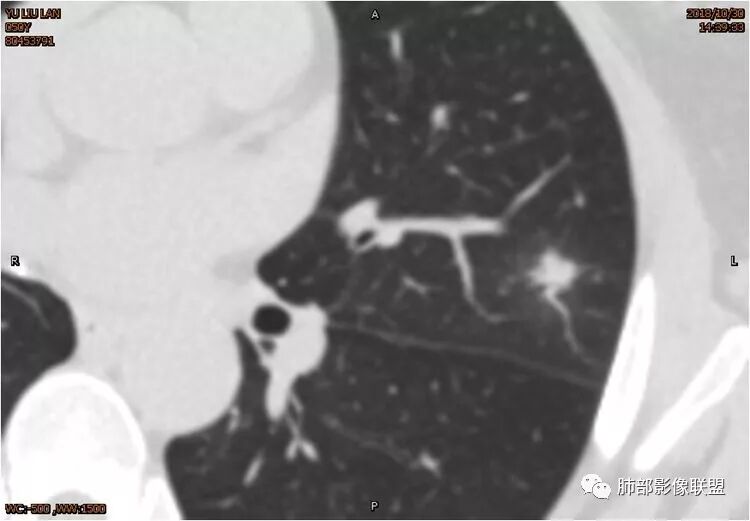

左肺上叶后段病灶,有毛刺,有胸膜牵拉,有血管滋养,好像还可以看见内部空泡,深分叶,边界比较清楚,考虑恶性肿瘤。

左肺上叶实性不规则结节,有深分叶,短毛刺,有切迹,有血管集束,有胸膜牵拉,常规考虑恶性,鉴别炎性结节

女性,左上肺实性结节,有毛刺,有血管进入,边缘彭隆,月牙铲,深分叶,边界比较清楚,胸膜牵拉,考虑腺癌。

左肺上叶结节,部分边缘膨隆,边缘毛刺,斜裂牵拉,增强中度强化,血管穿行,血管略增粗。考虑肺癌,腺癌可能性大,鉴别肉芽肿性炎

左肺上叶结节影,病灶周围呈磨玻璃样改变边缘见毛刺、分叶及胸膜牵拉,增强扫描病灶明显强化,病灶未跨叶间裂,考虑炎性病变,待除外小腺癌。

结节样病灶,u型征,病灶内可见细支气管管,增强可见血管进入,略增粗,病灶周围有晕,有软毛刺,局部叶间胸膜有牵拉,考虑良性炎性病灶,抗炎后复查。

细小毛刺,梳状平行,周围边缘模糊晕,血管未收侵犯,支气管未见牵拉扩张,多条淋巴道与胸膜相联,倾向于炎性病变

女性,50岁。U型凹陷、平直征

南边:支持炎性

1.胸膜下略不规则实性密度结节影,孤立,缺乏典型深分叶,可见淡薄边界模糊磨玻璃晕,可见相对细长软毛刺。

2.如南边老师分析,病灶缺乏边缘膨隆优势,甚至部分平直内收。

3.病灶收缩力不强,整体强化程度不显著。

4.综上,病灶更符合炎性,如隐球菌感染等,而不大符合肺腺癌。具体到机化性肺炎略有些出乎预料。